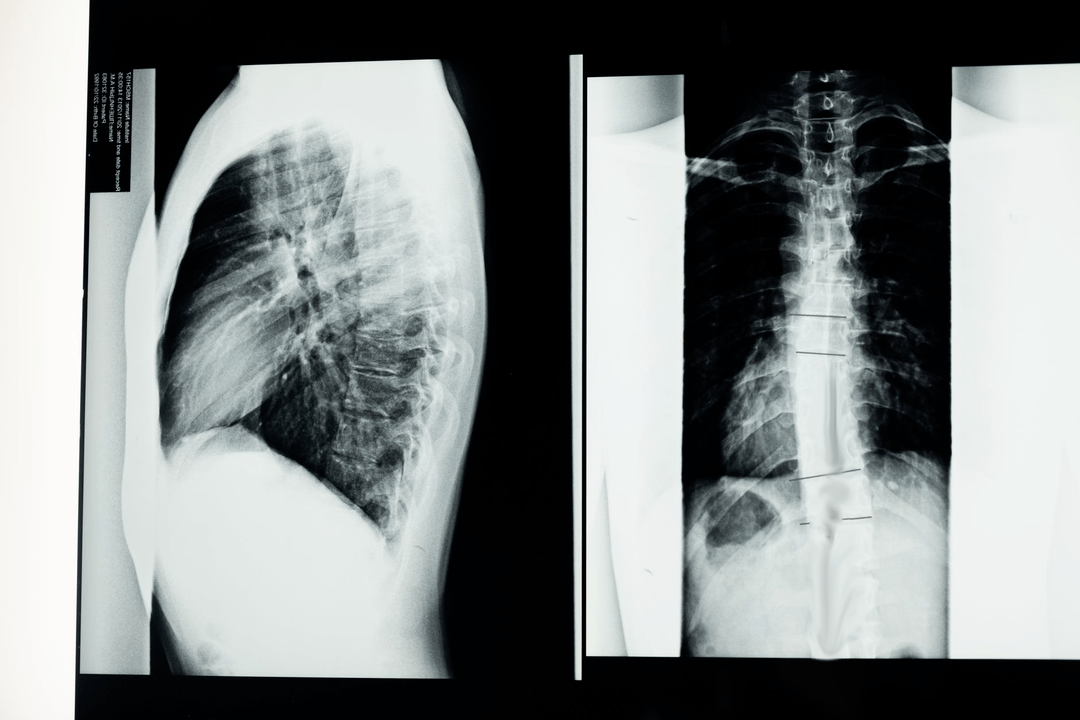

Prima di iniziare gli studi diagnostici, il neurologo raccoglie la storia medica del paziente e studia attentamente i suoi disturbi. L'osteocondrosi presenta sintomi comuni ad alcune altre malattie, quindi è importante essere in grado di differenziare le patologie. Gli studi a raggi X aiuteranno a confermare la diagnosi di osteocondrosi: radiografia, mielografia e tomografia computerizzata.

Una radiografia di rilievo permette di ottenere un'immagine radiografica della colonna vertebrale o di una sua sezione. In questo modo, il medico può determinare la sede interessata dalla malattia. Per chiarezza spiegheremo come si può determinare l'osteocondrosi mediante raggi X: l'immagine mostrerà un restringimento del disco intervertebrale, la presenza di escrescenze ossee (osteofiti) o un cambiamento nella forma del segmento spinale.